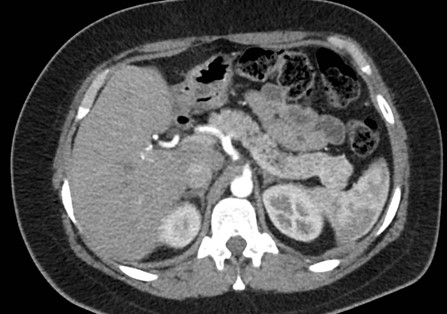

Caso 3

Mujer de 36 años que ingresa a Hospital Sanatorio Franchin el 11 de octubre de 2023 de forma programada para realización de duodeno pancreatectomía cefálica por tumor de cabeza de páncreas en estudio. Refiere hallazgo de lesión en forma incidental durante estudio de control hace dos meses por presentar antecedentes familiares (neoplasia endocrina múltiple). Se interna para manejo quirúrgico. Estudios de tomografía revelan formación nodular localizada en cabeza y cuerpo pancreático de paredes gruesas que mide 24 x 28 mm, que en resonancia se muestra hiperintensa en T2 y realce periférico luego de la administración de contraste endovenoso. Presenta restricción en la difusión con caída de la señal ADC, por lo que se vincula con una lesión de alta celularidad.

Laboratorios clínicos: Hto: 42 HB: 14.1 GB: 4200 Plaq: 231mil Glu: 90 Péptido C: 3.5 TGO: 17 TGP: 28 BT: 0.75 Fal: 179 Glucemia 109 TP: 100% KPTT: 36 Prots tots: 6.5 AlB 4.43.

Se le practica una duodeno pancreatectomía cefálica y triple anastomosis (hepato yeyuno, gastroentero y wirsung enteroanastomosis) el 12 de octubre de 2023 y pasa a internación UTI, el 14 de octubre se complica con fiebre, dolor abdominal y fístula pancreática con dosaje de amilasa de drenaje >6000, por lo que se le realiza tomografía que muestra abundante líquido libre en cavidad. Por tal motivo se le realiza una exploración quirúrgica por laparotomía, encontrándose abundante líquido + pancreatitis en la anastomosis yeyuno pancreática. Se realiza lavado de cavidad + 3 drenajes abocados a zona pancreática + yeyunostomia.

Paciente que se intuba y pasa a UTI, posteriormente extubación exitosa. El 22 de octubre se complica con colección abdominal, por lo cual requiere de drenaje percutáneo guiado por TC.

Paciente con evolución clínica favorable, el día 29 de octubre de 2023 se da egreso.

Tomografía de abdomen y pelvis con cte ev: del 13/10/2023.

Complicaciones posquirúrgicas

Tomografía de abdomen con cte ev: del 20/10/2023.

Tomografía de abdomen con cte ev: del 26/10/2023.

Estudio histopatológico reveló neoplásica de estirpe neuroendocrina bien delimitada.